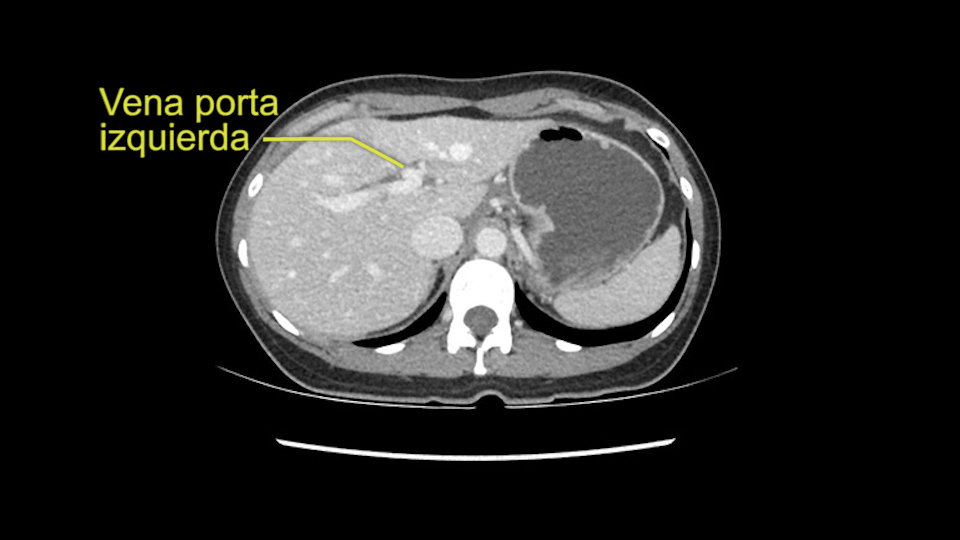

So the issue with regards to resection. A left sided tumor. I believe I can see the falciform ligament right here so we’re looking at a resection of Segments 2, 3 of the left lobe of the liver. The left portal vein is right there. I think we’ll be wiser to take the left portal vein and therefore get well into Segment 4 and do a left hemihepatectomy. Certainly, one does not need to take the middle hepatic vein; it’s miles from the tumor.

My plan would be to leave the caudate lobe intact. You usually have to divide the caudate branches. I can see one of the caudate branches here coming off the left portal vein. You usually have to take that to get adequate length although you might be able to divide the portal vein past that left caudate branch.

En cuanto a la hepatectomia izquierda aquí creo que la clave va a ser disecar bien el ligamento venoso y poder ir pasar una cinta alrededor de la vena hepática izquierda, en este caso parece que al vena hepática izquierda está muy junta, como en muchos casos a la vena hepática media, a ser importante disecar bien la vena supra hepática izquierda para poder pasar alrededor de ella sin dañar la cava o la vena hepática media. Una vez que hayamos hecho esto pasaremos a mirar la porta, y yo siempre tiendo a disecar las estructuras lo mas próximas al hígado posible, disecaremos la arteria hepática media rama del segmento 2-3 y la rama del segmento 4 si estamos haciendo una hepatectomia izquierda, y insisto parce que este tumor además tiene otras muchas ramas que van directas al tumor que habrá que ligar, eso nos dará acceso a la vena porta izquierda que probablemente resecare con una grapadora lineal, y finalmente transectarmos, haremos la transeccion hepática.